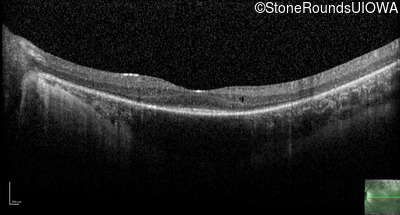

Optical Coherence Tomography - Left - 20/100 -1

Exemplar / OCT Stack